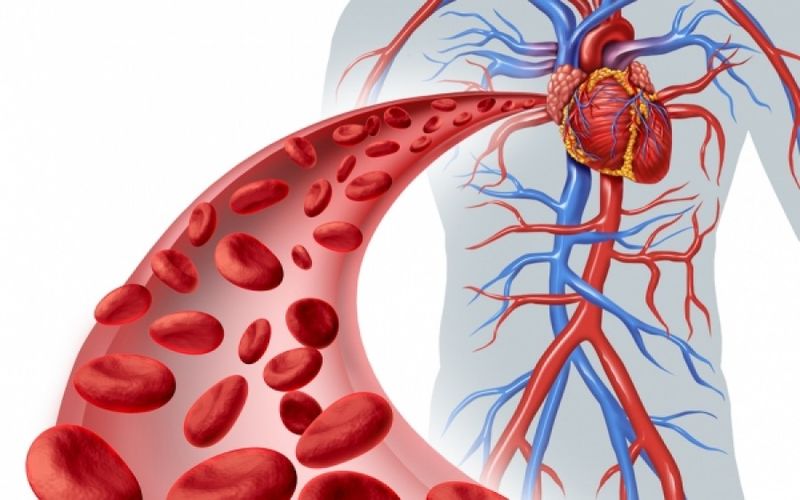

Αγγειίτιδα: Πρόκειται για μια φλεγμονή των αιμοφόρων αγγείων. Δηλαδή, μια πάθηση που προκαλεί αλλαγές στα τοιχώματα των αιμοφόρων αγγείων. Από εκεί και πέρα, οι αλλαγές περιορίζουν τη ροή του αίματος. Μάλιστα, αυτό έχει ως αποτέλεσμα να επέρχεται η σταδιακή καταστροφή των οργάνων, καθώς και των ιστών.